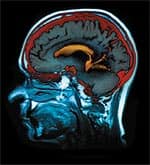

The horrible tragedy that took place on September 11, 2001, had special meaning for 32-year-old Amy Pomykal. A Dallas-based flight attendant for American Airlines, she was deeply saddened by the loss of her colleagues, but grateful that fate had been kind to her that day. In the month following the tragedy, she took a leave of absence from work, uncertain about whether she wanted to continue flying or what to do next. The only thing she could say for certain was, “life is short, I just want to live life.” It would prove to be a prophetic statement, one that would come back to haunt her just months later. Amy engaged in a whirlwind of experiences before her scheduled return to flying on May 1, 2002. She considered career changes, discussed starting a family with her husband Tim, worked two jobs, volunteered at a children’s hospital, and won the Mrs. Dallas County pageant. With a world of possibilities seemingly open to her, everything suddenly changed on Saturday, April 27, 2002. An Unforeseen TragedyAfter spending the day shopping with her sister Keri McClure, Amy felt unusually tired that evening. She shooed her concerned sister home and lay down on the sofa to relax. It would be the last thing she remembers of that day. Tim came home to find his wife curled in a fetal position on the kitchen floor. As he grabbed the phone to call 911, Amy had a seizure. She had two more seizures waiting for paramedics to arrive, then a fourth one on her way to Baylor Medical Center in downtown Dallas. Paramedics gave her Valium® to prevent brain damage. At the emergency room, the first diagnosis stunned Amy’s family. “They thought I was on drugs, because it was Saturday night at 9:30,” she says. “They didn’t do anything with me for several hours, thinking I’d come out of it, or that if it were epilepsy, the seizures would stop. But I didn’t come out of the state I was in.” Amy’s family was adamant that she did not drink or use drugs. The hospital kept her overnight and an MRI was ordered the following morning. Doctors quickly delivered the devastating news: they were 90% certain she had a brain tumor, and the prognosis was not good. “They said it was inoperable and malignant,” Amy recalls. “They basically told me my days were numbered. I tried to get off the bed to find a trash can or a bed pan to throw up in. I felt like I was going to die. I remember being angry.” Her physicians discussed performing a burr-hole procedure, in which a surgeon drills a small hole in the skull and inserts a needle to remove a tissue sample from the tumor to ascertain its type and thus how to treat it. However, Amy’s family was uncomfortable with the risky procedure. Amy herself was incapable of making decisions and unable even to speak because the tumor affected her brain’s speech center. Her husband and sister took over as her advocates. It proved to be a good pairing, Amy says. Her husband Tim was conservative and hesitant to leap into unknown territories; he wanted to take time to consider everything the doctors said. Keri was more daring, willing to seek out and try anything that might save her sister. Together, Tim and Keri balanced and helped each other keep perspective. A Proactive ApproachTheir first decision was to move Amy to another medical facility. Keri also took to the Internet to search for information. On a site called VirtualTrials.com, which provides information on clinical trials and treatments for brain tumors, she found what she was looking for. “I read firsthand patient experiences, including the journals of Ben Williams, a brain-cancer survivor from California,” Keri says. “He had so much information on supplements he took and why he took them, and he mentioned the Life Extension Foundation as an excellent resource for quality supplements.”

Surviving Surgery and ChemoAmy’s family still wanted more opinions and sought the right surgeon to perform the operation. Amy went to several medical centers, all within a week after her first seizure. They decided to have the surgery performed at the University of Texas Southwestern Medical Center, where they received yet another diagnosis: anaplastic glioblastoma, a type of tumor that develops from the glial cells composing the brain’s supportive tissue. This type of tumor is recognized as one of the most deadly of all, and Amy’s was growing rapidly. Surgery was scheduled immediately. The surgery took nearly eight hours. Amy recovered rapidly, and soon afterwards was able to walk and speak again. While not all of the tumor had been removed, Amy felt well and was upbeat. She went home to prepare for simultaneous chemotherapy and radiation to begin two weeks later, knowing that, statistically, her chances were not good. “Even with radiation and chemo, most people die from this type of tumor anyway,” Amy says. “You have to keep fighting it whatever way you can.” Amy surprised even herself with her stamina during chemotherapy and radiation, and she credits her supplement program. She had enough energy to play tennis twice a week, and after a month on radiation, she still had most of her hair. Amy stopped chemotherapy in November 2002. Although her doctors spoke optimistically, she knew there was nothing more they could do for her. Still feeling fine, she ran a marathon on December 2. “Probably not the brightest thing I’ve ever done,” she says. “But I lived through it. I visualized my tumor shrinking, visualized myself being older. I prayed a lot for strength and the ability to make good decisions.”

A Promising VaccineTrying to decide what to do next, Keri learned of cutting-edge clinical trials of a cancer vaccine at the Brain Tumor Center at Duke University Medical Center. She wanted her sister to get into the trial of the dendritic cell vaccine, under the direction of John Sampson, MD, PhD. Dendritic cells trigger an immune response by activating killer T cells against foreign substances, such as bacteria, viruses, and tumors. Studies have shown that if the patient’s dendritic cells are cultured with RNA from the patient’s tumor, they produce a strong immune response against the cancer cells. Although the trial was closed, Dr. Sampson opened it for Amy. Supplement tackle box in hand, Amy flew to Duke for her first injection in late May 2003 and every two weeks thereafter for six weeks, receiving the last dose on July 21. She returned to Duke three months later for an MRI, and the scan showed definite improvement. Returning again in January 2004 for another scan, her doctors had a surprising announcement. “They said they don’t use the words ‘cure’ or ‘remission’ for brain cancer, but said ‘for right now, you’re cured,’” says Amy. “They said the tumor’s not there anymore. All that showed up on the scan was a small spot they thought was probably scar tissue from the surgery.” Henry Friedman, MD, co-director of the center’s clinical neurooncology program, says that empowering patients about their care is the way to achieve the best results. To that end, patients are permitted to continue alternative treatments they believe in, as long as they are honest about what they are taking and nothing they take has a known toxicity. “We have no proof that what she’s doing might hurt her, and it might help her. We don’t know the answer,” says Friedman. “We could say the same things about what we’re doing. I think it’s enlightened medicine. It’s admitting where you don’t know what’s going to go on, yet following ‘Do no harm.’” Amy believes she is cured. She receives periodic MRIs and looks forward to her visits to Duke. Although she has some memory deficit, occasionally has to search for words, and still takes anti-seizure medication, those around her say she is the picture of health, and she has even returned to her job at American. Nevertheless, Amy is ever mindful that life is precious. She no longer lets little things bother her. She is thinking once again about starting a family. She has adjusted her priorities. And she still takes her supplements. “I believe the supplements did a lot, and I know I’ll be taking them for the rest of my life,” she says. “I think it’s amazing that I was given such a diagnosis and I’ve done well through the whole thing. I believe it’s my supplements, my mental attitude, and my faith. I believe that I’m going to live. I’m going to survive.”